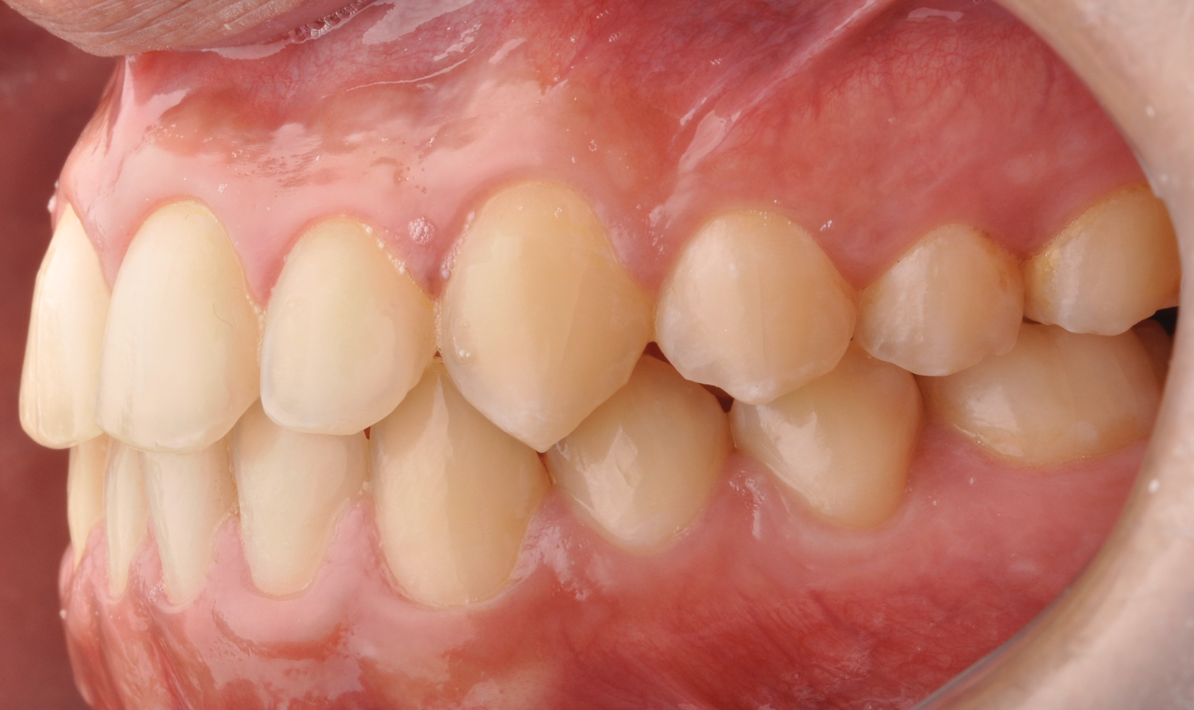

Fig 13. Dental views of the patient 3 years after surgical-orthodontic correction; right lateral view (Fig 13), frontal view (Fig 14), and left lateral view (Fig 15).

Figure 13